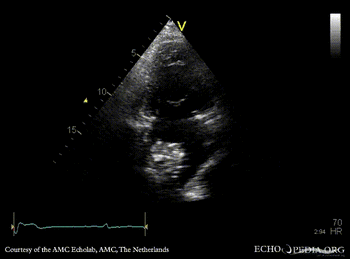

| PLAX: dilated left ventricle, myxoma in left atrium | PLAX: dimensions of myxoma |